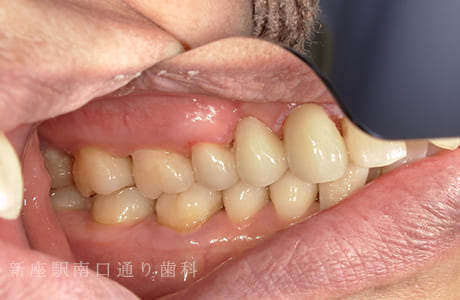

CASE.04

右上にフルジルコニアブリッジで

修復した症例

-

術前

術中

術後年

- 主訴

- 歯がないところを治したい

- 治療法

- 右上にフルジルコニアブリッジで修復

- 治療期間

- 1ヶ月半

- 費用

- ¥280,000(税込)

【リスク・副作用】

過度の咬合や衝撃で割れることがあります。治療直後は歯や歯茎に一時的な違和感や痛みが出ることがあります。